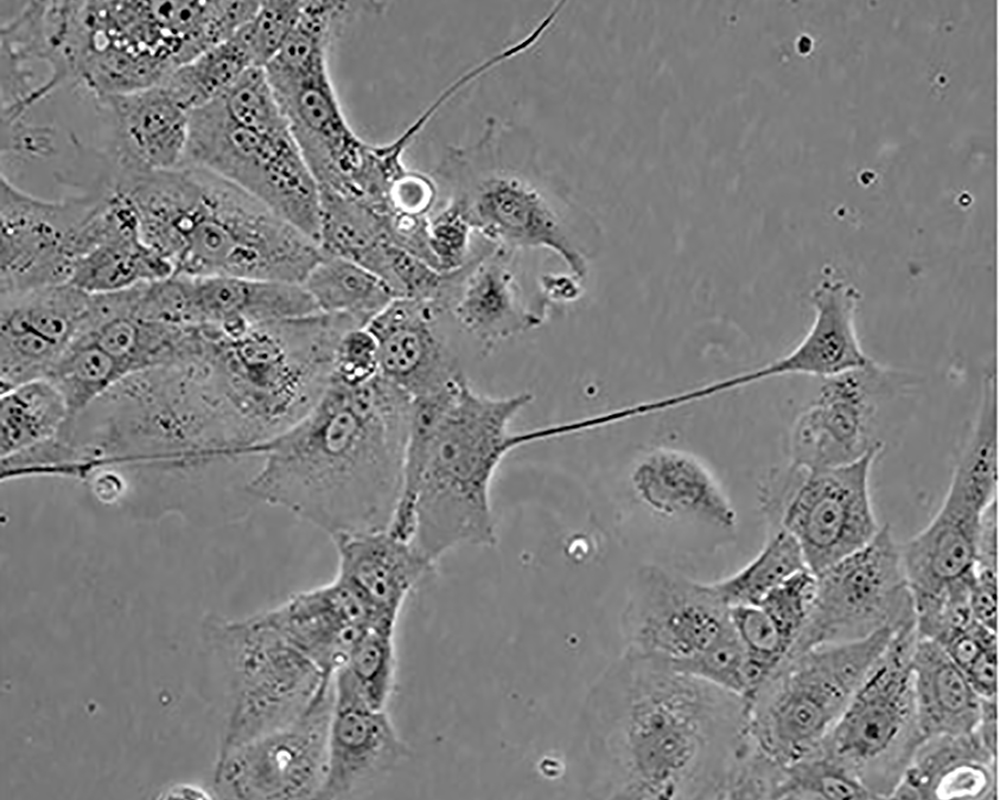

HCC827

產(chǎn)品名稱(chēng) HCC827

中文名稱(chēng) 人非小細(xì)胞肺癌細(xì)胞

生長(zhǎng)特性 adherent

形態(tài)特征 epithelial

細(xì)胞描述 This lung adenocarcinoma has an acquired mutation in the EGFR tyrosine kinase domain(E746-A750 deletion).